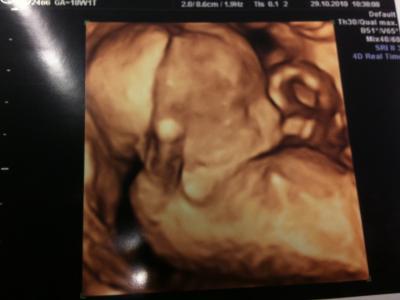

Huhu, kam leider nicht früher zum schreiben, waren ja am Freitag beim FA zur Kontrolle und alles super mit der Kleinen Die Kleine bleibt auch noch eine Kleine und wiegt 233g und ist 17 cm groß und liegt genauso im Bauch, wie die Mama im Bett, immer schön die Arme am Kopf Nächste Woche haben wir dann die FD, da freue ich mich riesig drauf :-) Gruss Sandra